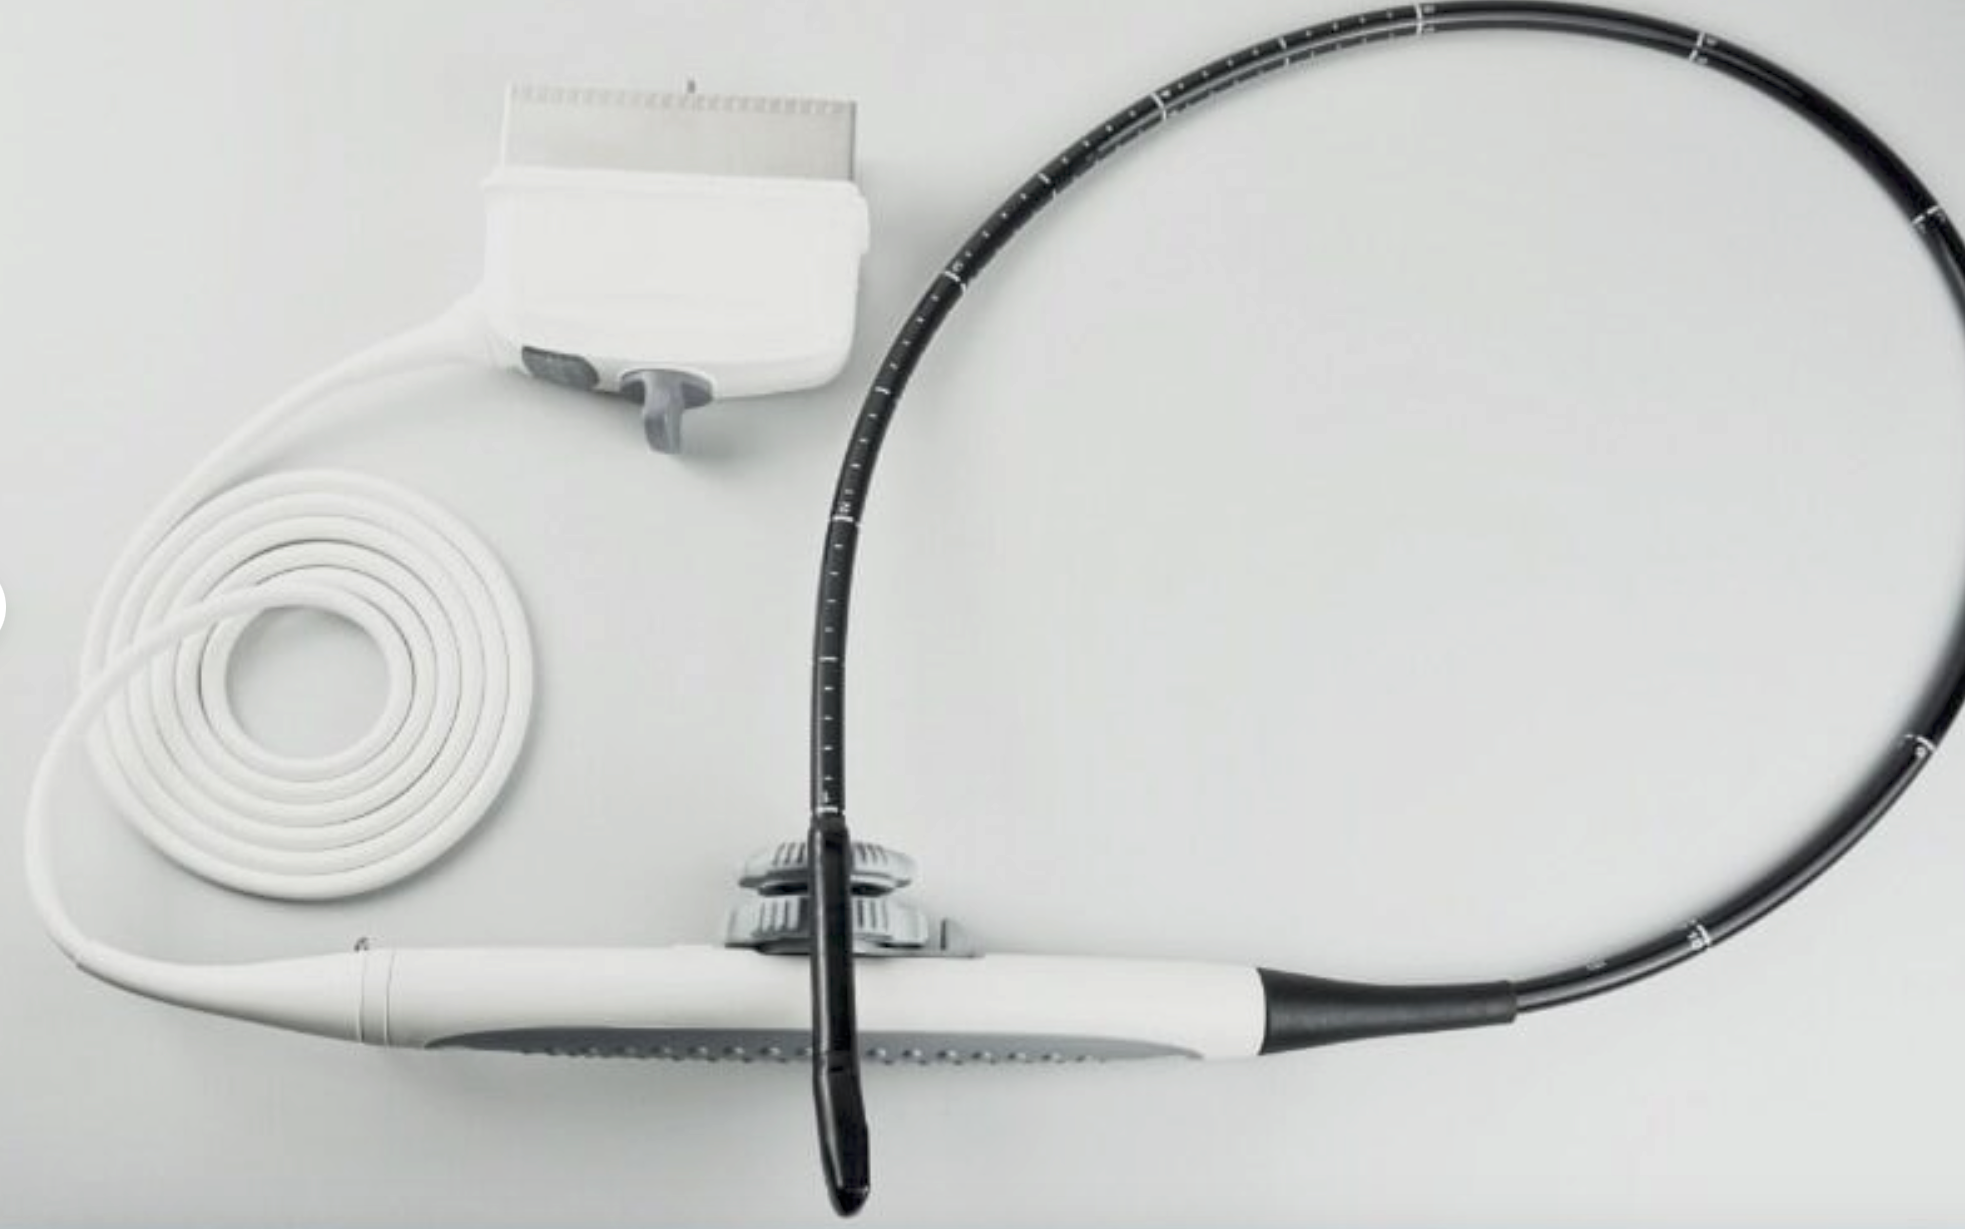

SONOSITE MicroMaxx Probe convex Transducer C60E

Sale price$ 1,638.36